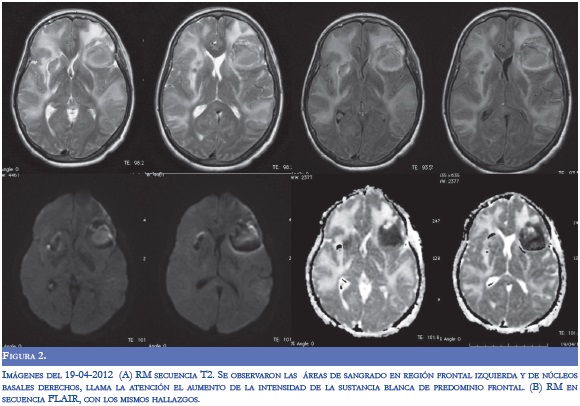

En la evaluación por neurología persistió disnéica con uso de musculatura intercostal, taquipnéica (FR: 32), taquicárdica (120) e inestabilidad hemodinámica (TA: 90/70), alerta con tendencia a la somnolencia, conteo vocal en 13, hipofonía, cuadriparesia 3/5 simétrica e hiporreflexia en 4 extremidades con respuesta plantar felxora bilateral. Se diagnosticó crisis miasténica, con inminencia de falla ventilatoria por lo cual se inició tratamiento con inmunolglobulina G humana y traslado a UCI. Durante la estancia hospitalaria, la paciente presentó respuesta inflamatoria sistémica, con aumento significativo de reactantes de fase aguda y enzimas hepáticas, secundario a bacteremia por Gram negativos, con requerimiento de soporte vasoactivo. Dos días después de finalizar manejo con inmunoglobulina, presentó focalización neurológica con mirada tónica hacia la izquierda, sin respuesta a estimulo externos, ni respuesta nociceptiva. Se realizó TC cerebral donde se evidenció sangrado en región frontal izquierda, otro en región cerebelosa derecha, ambos con edema perilesional, y disminución en la densidad en la sustancia blanca con aspecto de edema vasogénico (Figura 1). En la RM cerebral simple y contrastada se observaron lesiones hiperintensas subcorticales bilaterales con áreas de hemorragia (Figura 2). Se realizó panangiografia cerebral con vasoespasmo de la ACM izquierda M1 y ACA A1 derecha sin patrón de vasculitis. Durante su estancia hospitalaria presentó mejoría clínica y a las dos semanas se observó mejoría del edema vasogénico en las neuroimágenes (Figura 3).

La localización usual del PRES se circunscribe a las áreas de la circulación posterior sin compromiso hemorrágico. Sin embargo se han descrito localizaciones atípicas en el siguiente orden de frecuencia: núcleo basales, tálamo, lóbulo frontal y tallo cerebral; también no solo presentan edema vasogénico el cual se representa hiperintenso en el mapa ADC y la difusión, sino que puede presentar otras lesiones de tipo isquémico, citotóxicas, hemorrágicas o realce anormal con el contraste en las neuroimágenes (3).